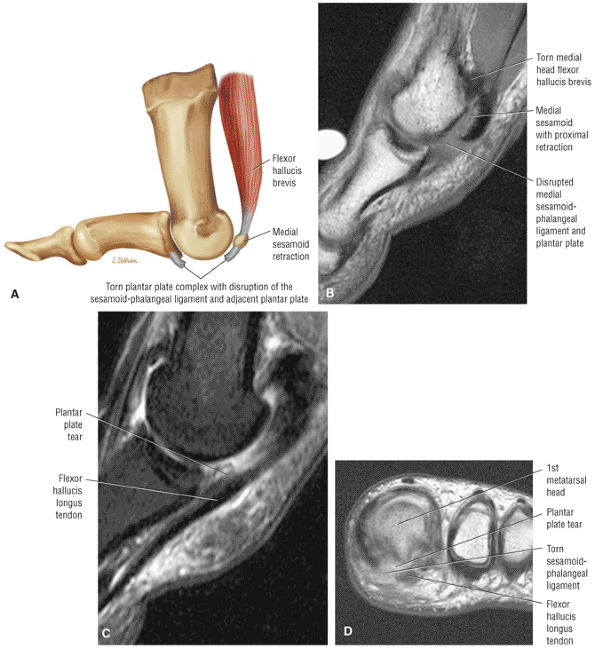

FIGURE 5.20 ● FLEXOR HALLUCIS BREVIS The flexor hallucis brevis functions in flexion of the great toe. Instability of the first metatarsophalangeal joint occurs with loss of flexor hallucis brevis function, as occurs with excision of both tibial and fibula sesamoids.